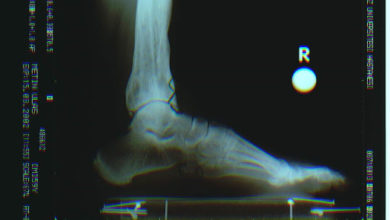

Topuk kemiği kırığı (kalkaneus kırıkları)

En sık kırılan ayak kemiğidir Kırıklar eklem içi ve eklem dışı olarak gruplanır. Sıklıkla yüksekten düşme sonucu gözlenirler. Prof. Dr. Mustafa…